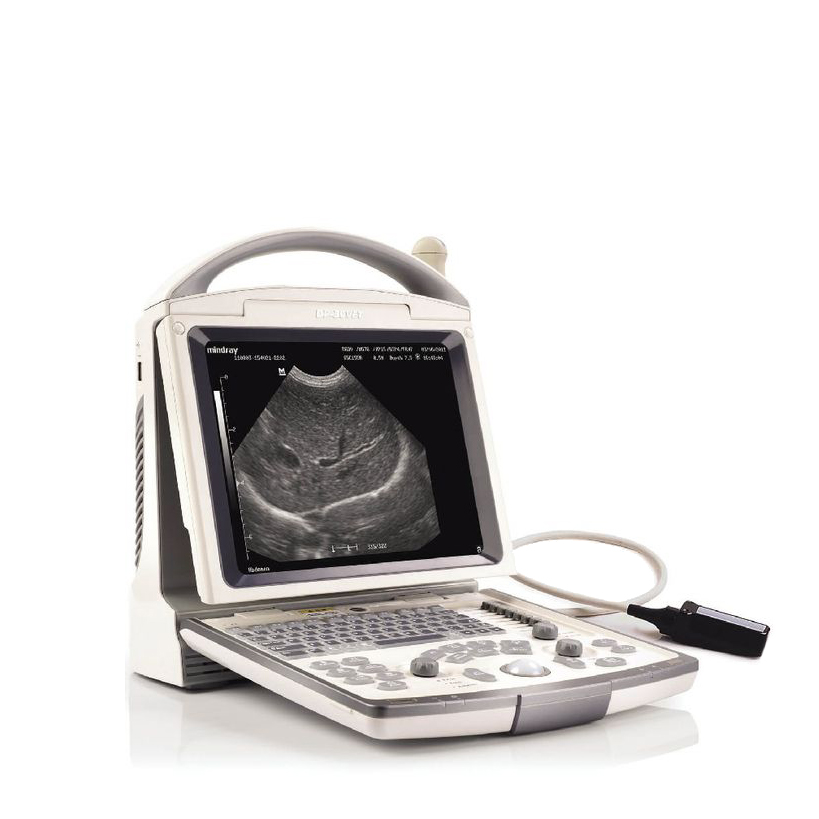

УЗИ аппараты

УЗИ аппараты

УЗИ аппараты

УЗИ аппараты

УЗИ аппараты

УЗИ аппараты

УЗИ аппараты

УЗИ аппараты

УЗИ аппараты

УЗИ аппараты

УЗИ аппараты

УЗИ аппараты

УЗИ аппараты

УЗИ аппараты